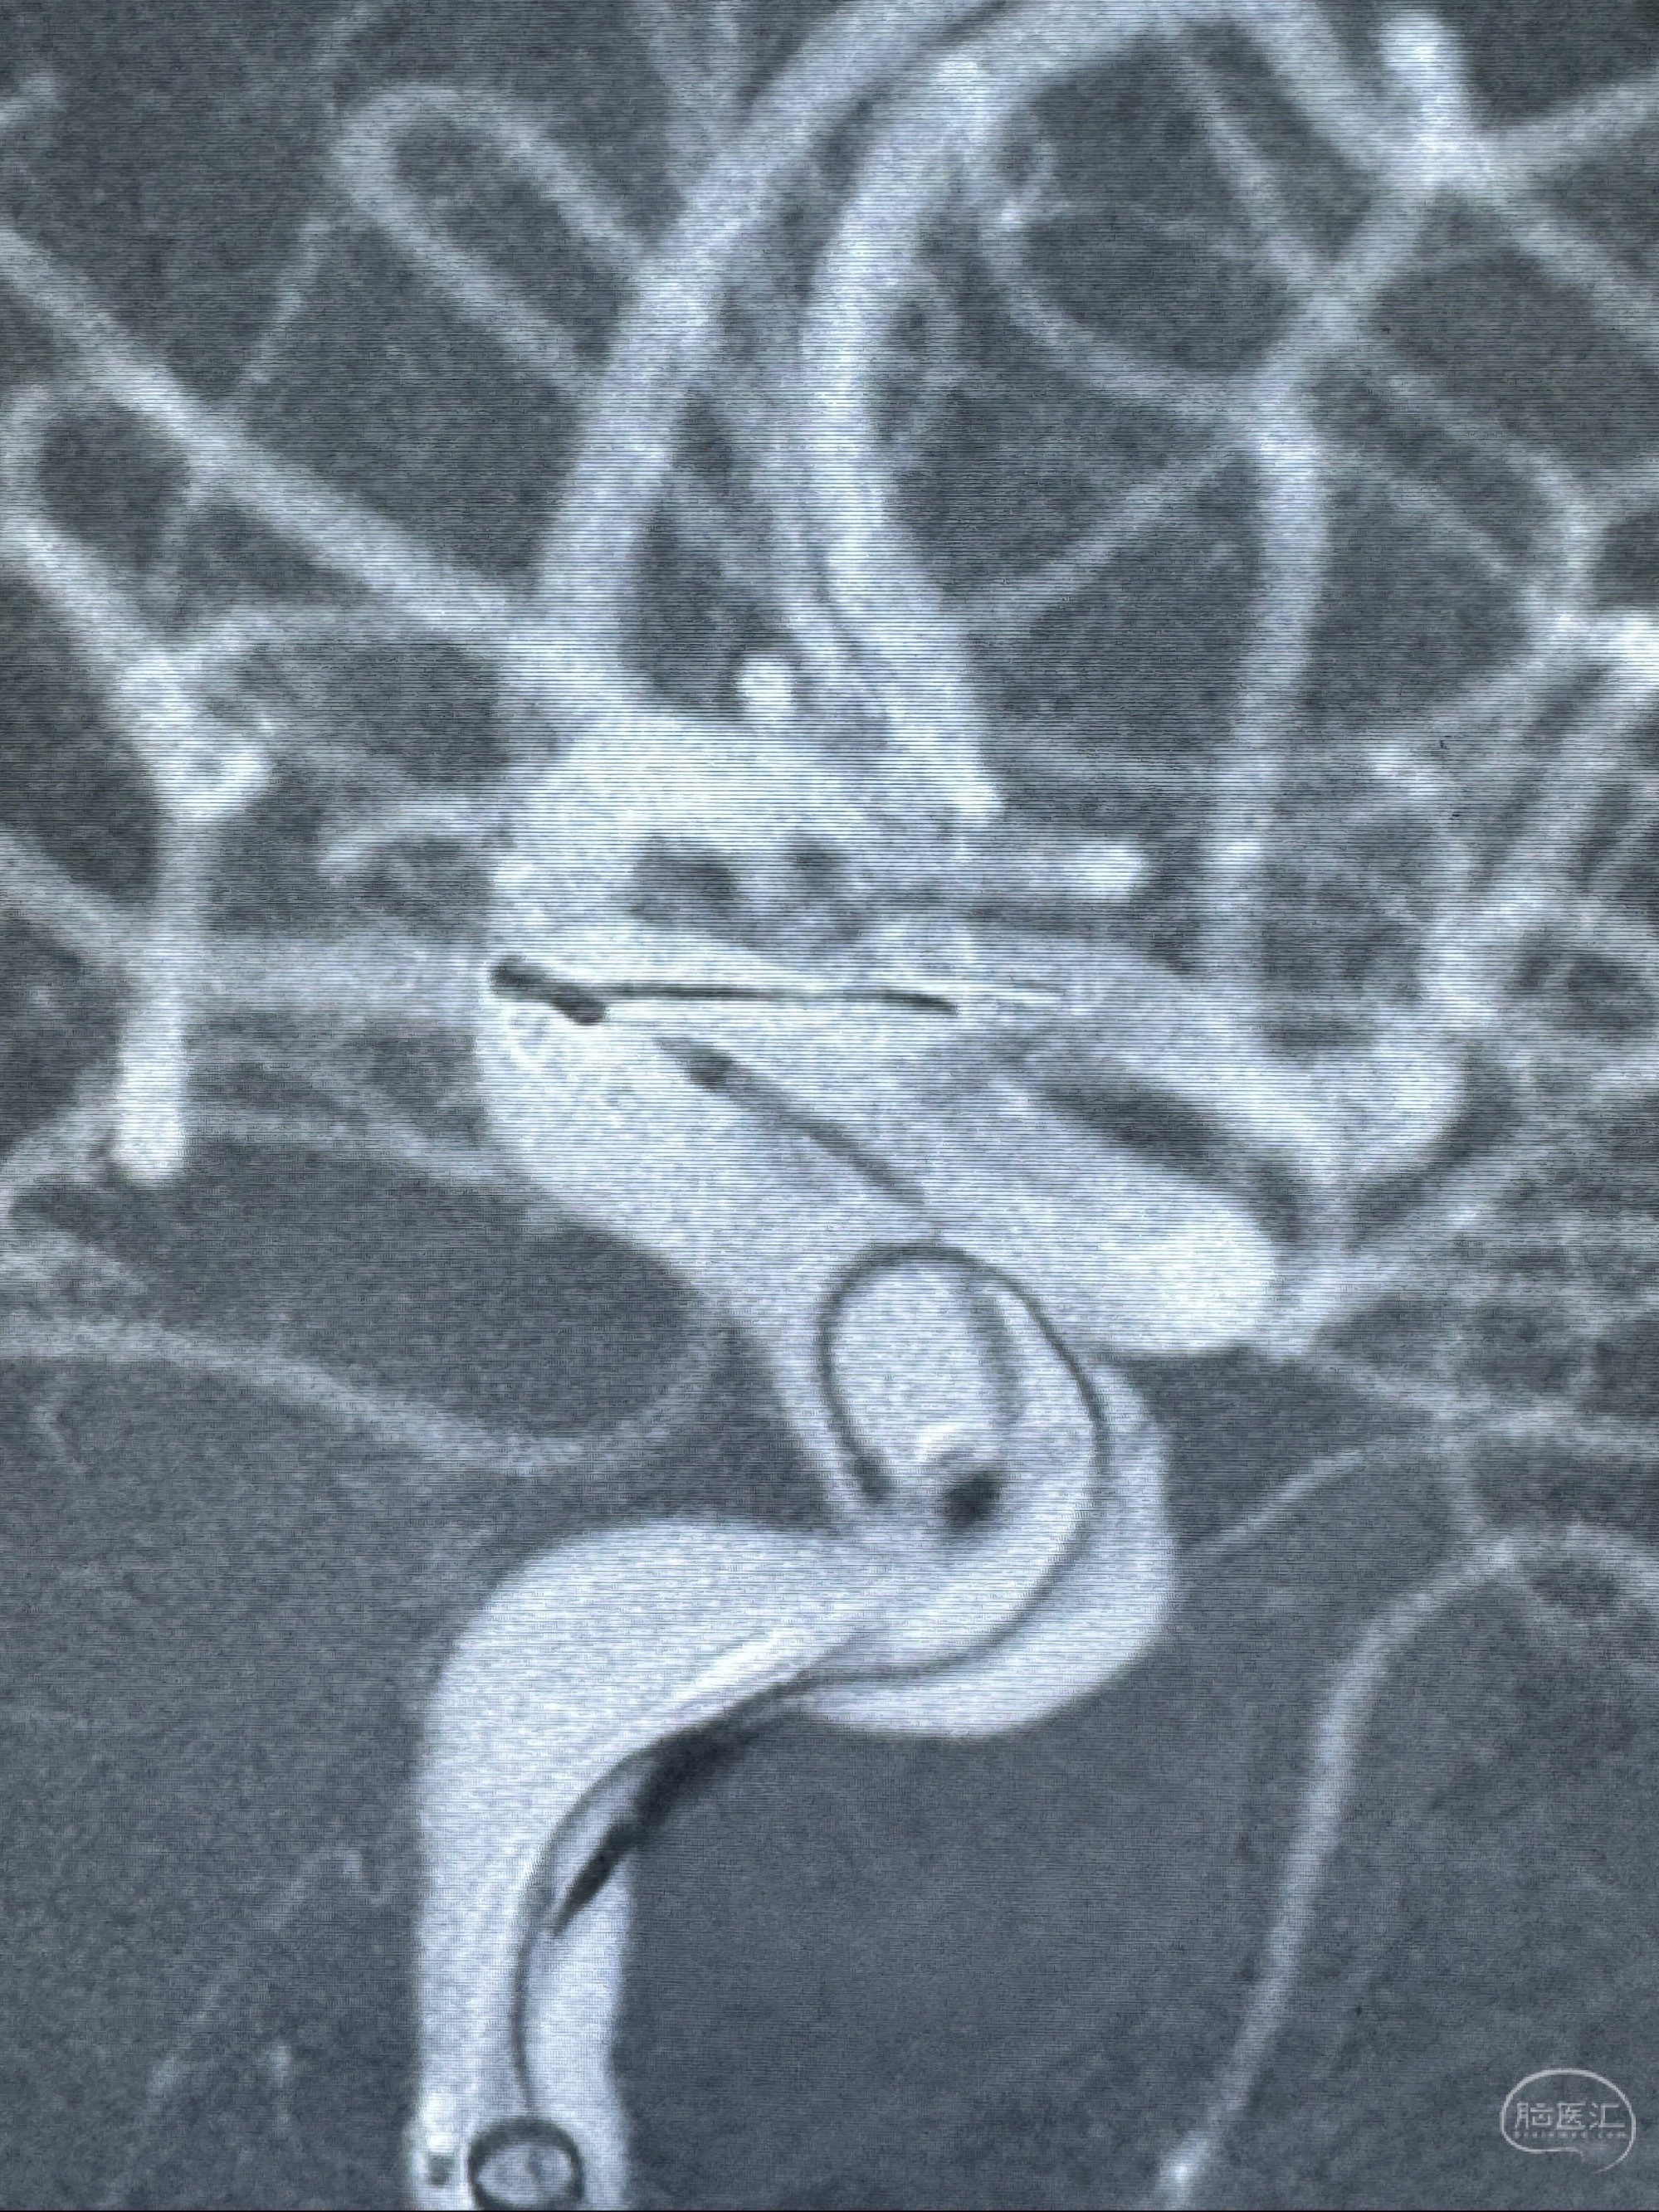

2023-11-13DSA:左侧颈内动脉眼动脉后壁动脉瘤

2023-11-29全麻下行NeuroformEZ4.5-20mm支架辅助栓塞